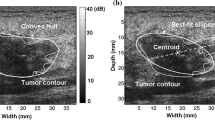

Image selection for radiomics analysis

One typical ultrasound image which mostly matches with the morphologic description of the breast mass was selected for each patient to perform computer-aided radiomics analysis. Firstly, the region of interest (ROI) delineating margins of the mass was outlined on the selected ultrasound images by the ultrasound physician ZJ Zhao for radiomics feature analysis. The data set was randomly divided into the training set and testing set at a ratio of 7:3. Figure 1 shows the flowchart of the computer-aided radiomics analysis.